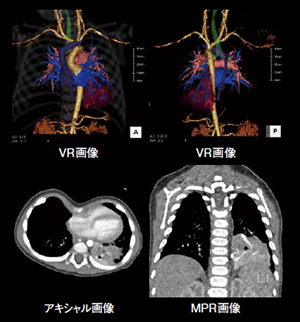

低管電圧(80kV)を使用した胸部CTA

【背 景】70歳代,男性。肺アスペルギルス症にて外来通院中に喀血出現。肺実質の炎症性病変の分布,気管支動脈-肺動脈シャントの評価,経カテーテル的治療に必要な血管解剖の把握を目的に,低管電圧(80kV)を使用した胸部CTAを施行した。

【所 見】肺野に著明な気腫性変化があり,ブラが散見された。左上葉の気管支拡張と炎症瘢痕形成が認められた。造影CTでは両側気管支動脈が発達しており,左気管支動脈は一部拡張蛇行している。逆行性に造影される左上葉肺動脈が描出され,気管支動脈-肺動脈シャントも確認できた。

【訴求ポイント】(1) 造影剤注入方法:24 mgI/kg/sを採用し,秒間4.0 mL以上で10秒急速注入。(2) 生理食塩水の後押し:秒間4.5 mLで4.4秒,20 mLの生理食塩水を注入。目的となる血管の描出能が向上した。(3) 管電圧:80kVの低管電圧を選択し,CARE kVのSemi modeで撮影。コントラストの向上と被ばく線量の低減を実現。(4) 術前プランニング画像:ワークステーションにて画像を作成。IVRの被ばく低減に寄与した。

胸部CTAにより気管支動脈-肺動脈シャントを良好に描出することができた。Right Doseテクノロジーを駆使することで,低管電圧,低ヨード造影剤量,低被ばく,IVRの被ばく低減が可能であった。